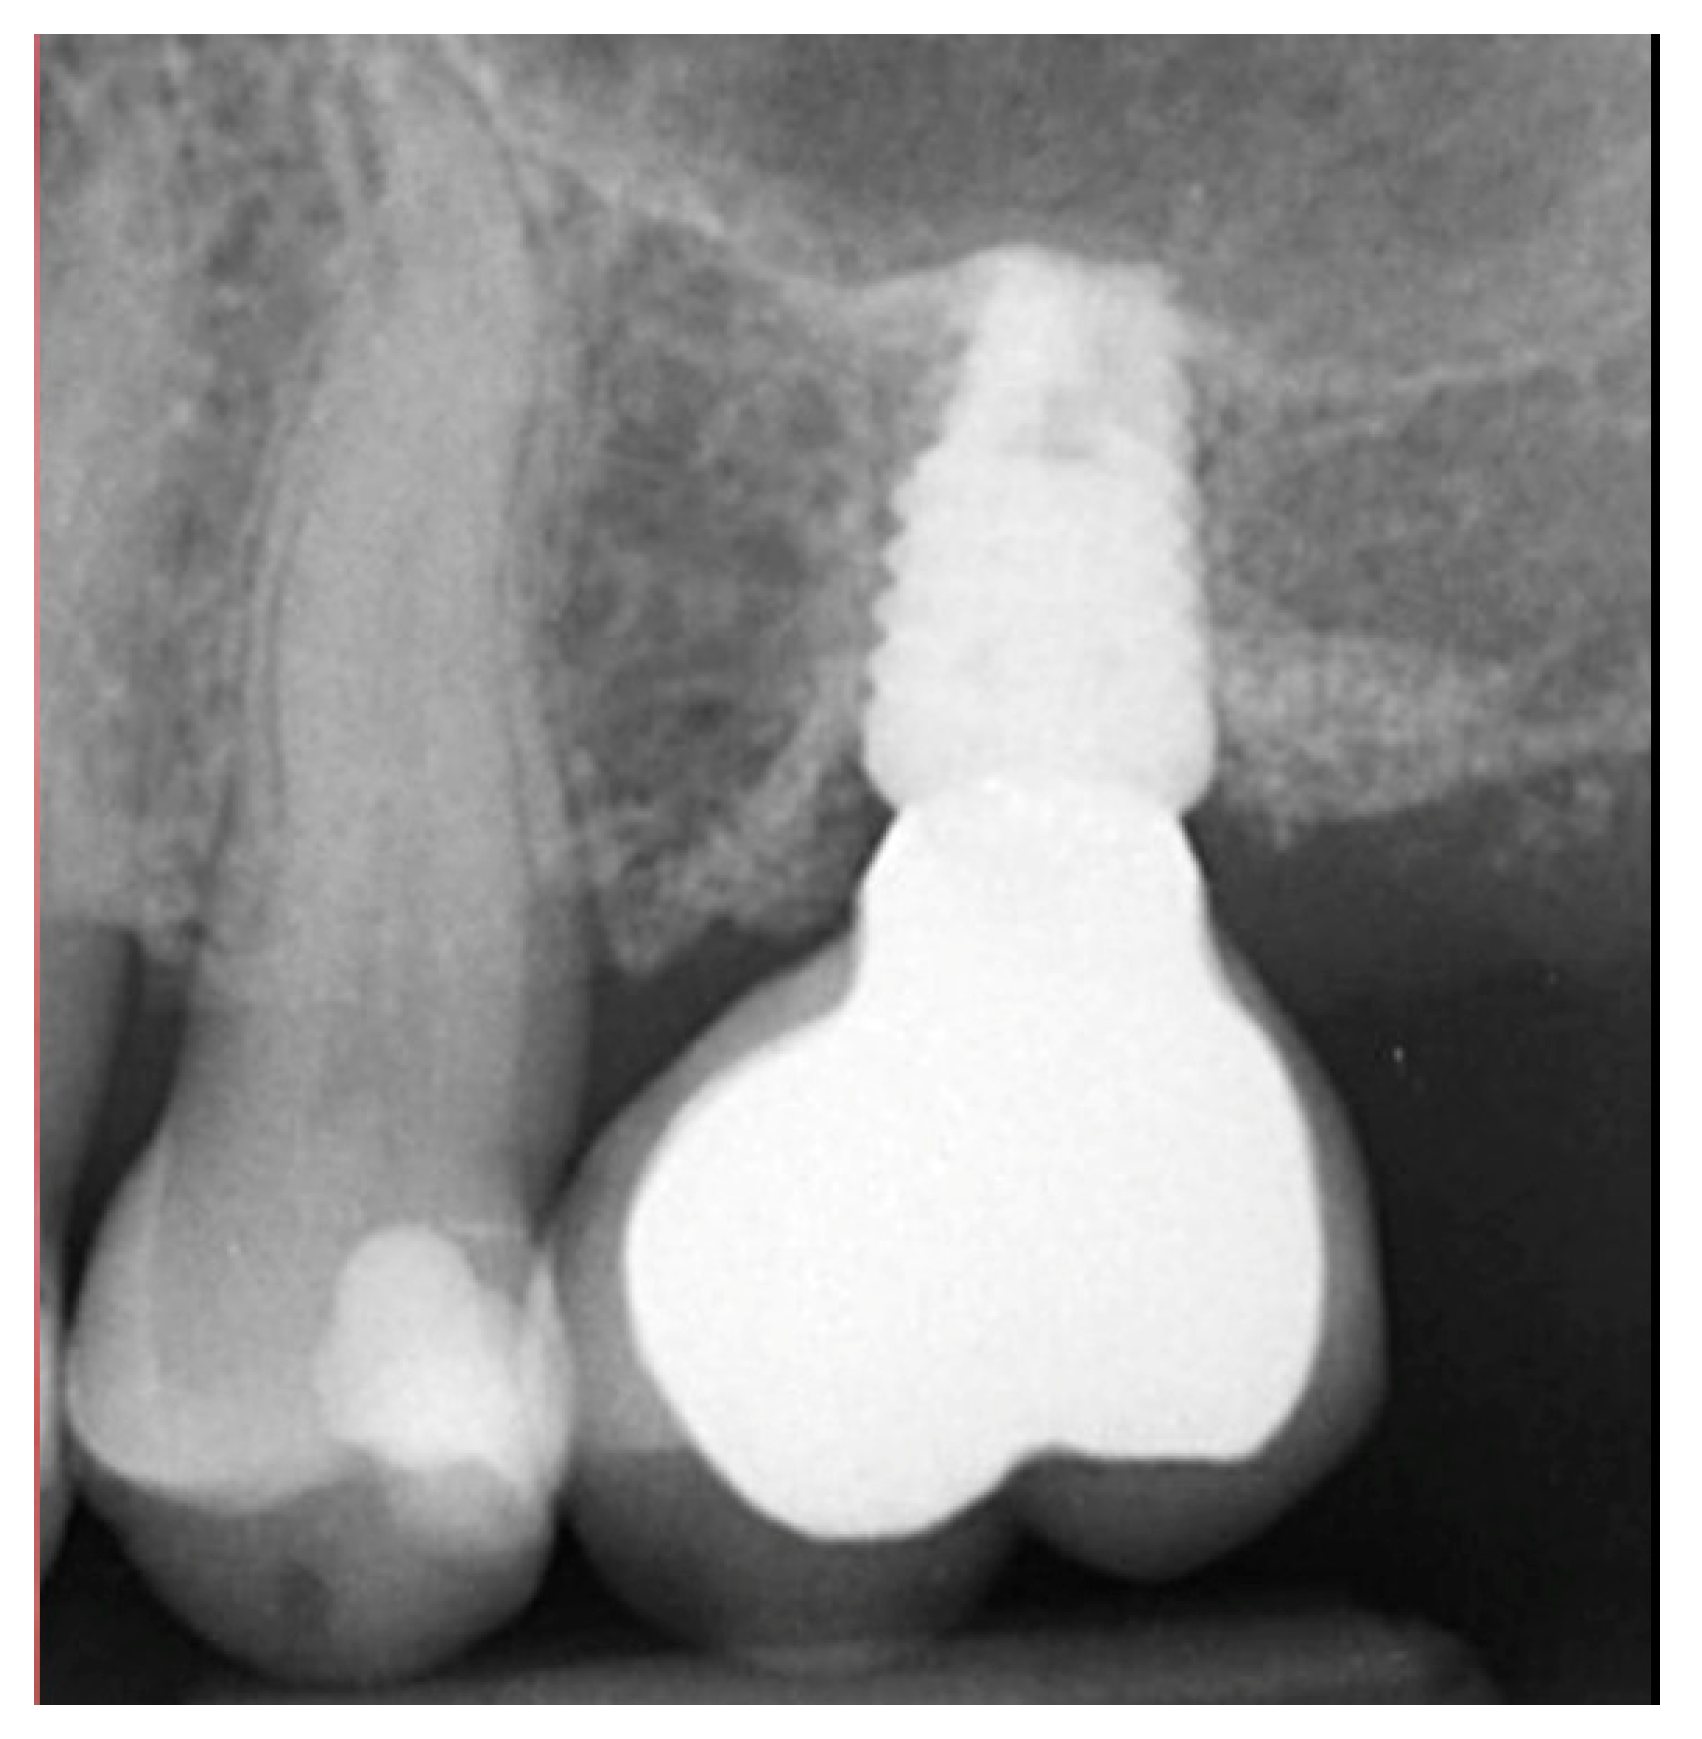

Figure 9.

Site was reentered at 10 weeks post-extraction and an implant was placed with a crestal sinus augmentation utilizing EthOss graft material at the 1st molar site and a large defect was present at the 2nd molar site (left), with a radiograph obtained to document the implant placement at the 1st molar and grafting of the defect (middle) and following crestal grafting of the 2nd molar site (right). Green line is the measurement of the height of the bone at that point between the crest and the sinus floor.

Local anesthetic was administered, and a full thickness flap of the area was elevated. Utilizing a similar technique as outlined in case 1, the 1st molar site underwent a crestal lift and a 4.5 × 8.5 mm Anyridge (Megagen, Busan, Republic of Korea) implant was placed (Figure 9). The defect present at the 2nd molar site, resulted in a crestal height of 1.5 mm, which was insufficient for implant stability if a simultaneous crestal sinus left was performed (Figure 9, middle). Thus, grafting would need to be performed to prepare the site for later implant placement. EthOss graft material was hydrated in the syringe as previously described and placed into the defect to increase crestal height following healing (Figure 9, right).